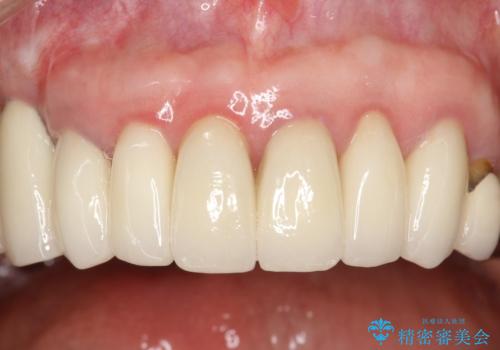

前歯の低クオリティな治療の実態 妥協無い治療で根本からやり治す

時間をかけ、妥協なく治療を行い、今後の再治療の可能性を極力少なくするために、

費用や時間といった労力がかかってしまうのは当然のことです。

かぶせ物の種類:PFZ standard